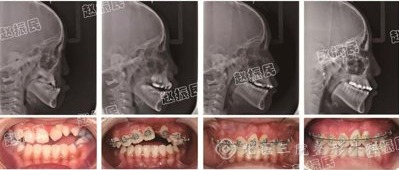

经缝牵引成骨技术矫正儿童颅面骨骼发育不全

自动持续经缝牵引成骨技术,就是施加一种力自动持续作用在生长发育期的面部骨骼和骨缝上,刺激骨骼干细胞再生出新生骨组织,促进面中部骨骼三维方向的生长,通过骨组织自身再生达到治疗上颌后缩、面中部发育不全或由此造成的反咬合。让患儿能够恢复正常的咀嚼功能、语言功能、消化功能和容貌功能,通过建立正常的咬合功能,使患儿的面型获得正常生理性的发育,使患儿的下颌关节功能得到保护和正常发育。